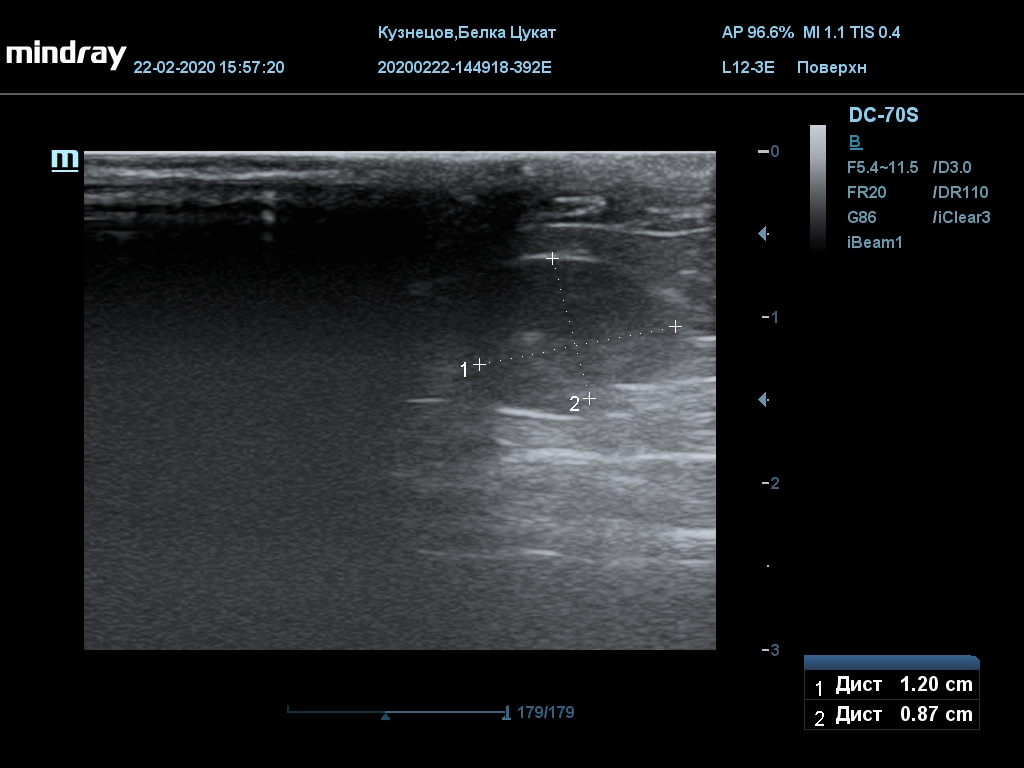

УЗИ

(почки, мочевой пузырь и, предположительно, простата)

Обращаю внимание, что делала УЗИ и писала заключение узист, которая специализируется на кошках и собаках, поэтому она сделала узи и описала, как смогла, но тонкостей грызунячьей анатомии она не знает.

Приложил только фото, есть ещё пара видео, но не знаю, как тут выложить, и надо ли.

Мочевой пузырь объём 12,1 х 7,6 х 11 мм. Стенка не утолщена, 0,5 мм, содержимое не однородное, до половины объёма гипоэхогенная мелкодисперсная взвесь. Макс. размер включений 0,8 мм. Теней нет.

Каудальнее мочевого пузыря визуализируется округлая структура размером 11,1 х 8,3 мм с ровными контурами гипоэхогенная однородная, с признаками васкуляризации.

Почка левая ровная, размер 12 х 7,6 х 8,2 мм. Контур ровный чёткий. КМД отсутствует, лоханка расширена незначительно, объёмных включений не выявлено.

Почка правая ровная, контур чёткий, размер 13,5 х 8,7 х 9,3 мм. Капсула визуализируется. КМД отсутствует, лоханка не расширена. Объёмные образования не выявлены.

Заключение: УЗпризнаки уролитиаза, объёмная структура каудальнее мочевого пузыря. Признаки расширения левой лоханки.

УЗИ

(почки, мочевой пузырь и, предположительно, простата)

Обращаю внимание, что делала УЗИ и писала заключение узист, которая специализируется на кошках и собаках, поэтому она сделала узи и описала, как смогла, но тонкостей грызунячьей анатомии она не знает.

Приложил только фото, есть ещё пара видео, но не знаю, как тут выложить, и надо ли.

Мочевой пузырь объём 12,1 х 7,6 х 11 мм. Стенка не утолщена, 0,5 мм, содержимое не однородное, до половины объёма гипоэхогенная мелкодисперсная взвесь. Макс. размер включений 0,8 мм. Теней нет.

Каудальнее мочевого пузыря визуализируется округлая структура размером 11,1 х 8,3 мм с ровными контурами гипоэхогенная однородная, с признаками васкуляризации.

Почка левая ровная, размер 12 х 7,6 х 8,2 мм. Контур ровный чёткий. КМД отсутствует, лоханка расширена незначительно, объёмных включений не выявлено.

Почка правая ровная, контур чёткий, размер 13,5 х 8,7 х 9,3 мм. Капсула визуализируется. КМД отсутствует, лоханка не расширена. Объёмные образования не выявлены.

Заключение: УЗпризнаки уролитиаза, объёмная структура каудальнее мочевого пузыря. Признаки расширения левой лоханки.